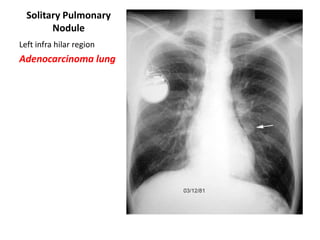

Solitary Pulmonary

Nodule

Left infra hilar region

Adenocarcinoma lung